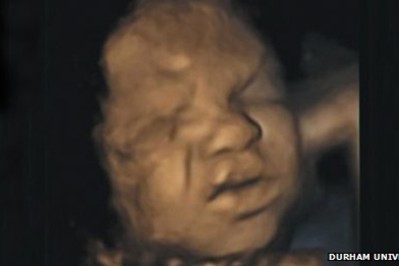

Już w brzuchu przyszłej mamy maleństwo uczy się komunikować za pomocą płaczu oraz grymasów twarzy - twierdzą badacze z Uniwersytetu Durham.

Ich szczegółowe badanie wykonane za pomocą USG pokazuje, że dzieci jeszcze przed przyjściem na świat wykonują mnóstwo ruchów twarzy - od uśmiechania się po obniżanie brwi czy marszczenie noska.